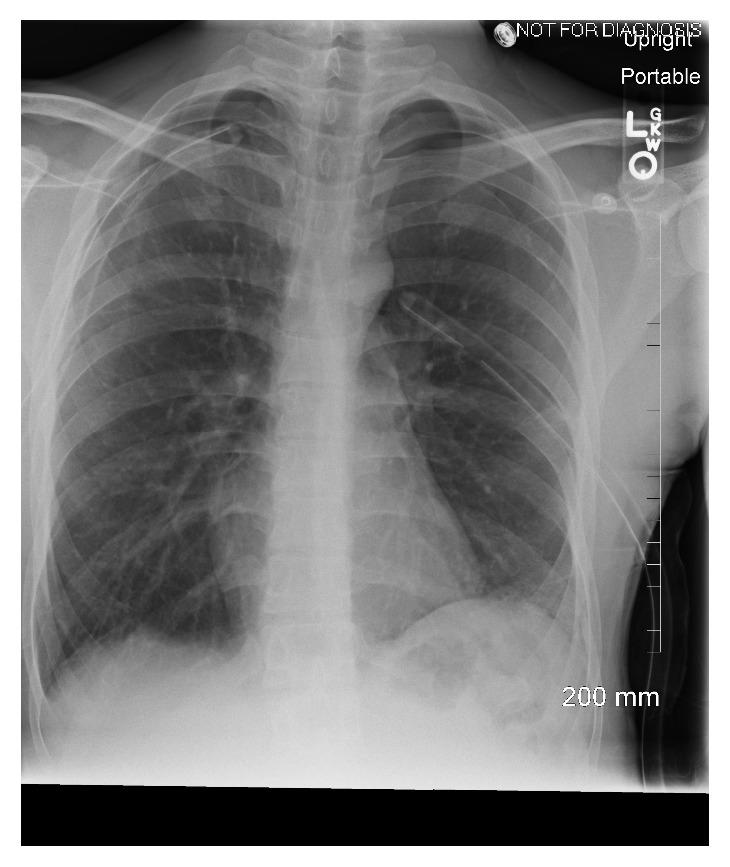

A 21-year-old man with a past medical history of well-controlled intermittent asthma presented with acute worsening shortness of breath overnight. Chest X-ray performed showed bilateral large pneumothorax with significantly compressed mediastinum. Chest tubes were placed bilaterally with immediate clinical improvement. However, the chest tubes continued to have an air leak without full lungs expansion. Computed tomography scan without contrast of the chest revealed subpleural blebs in both upper lobes. The patient underwent bilateral video-assisted thoracoscopic surgery (VATS) with apical bleb resection, bilateral pleurectomy, and bilateral doxycycline pleurodesis. Biopsy of the apical blebs and parietal pleura of both lungs were negative for any atypical cells suspicious for malignancy or Langerhans cell histiocytosis. The patient had been doing well six months following surgery with no recurrence of pneumothorax.

一名21岁男性,既往间歇性哮喘病情控制良好,一夜之间突发急性呼吸困难加重。胸部X线检查显示双侧大量气胸,纵隔明显受压。双侧置入胸腔引流管后临床症状立即改善。然而,胸腔引流管持续漏气,肺部未完全复张。胸部非增强计算机断层扫描显示双上叶胸膜下肺大疱。患者接受了双侧电视辅助胸腔镜手术(VATS),包括切除肺尖肺大疱、双侧胸膜切除术及双侧多西环素胸膜固定术。双肺肺尖肺大疱及壁层胸膜活检未发现任何可疑恶性或朗格汉斯细胞组织细胞增多症的非典型细胞。患者术后6个月情况良好,气胸未复发。